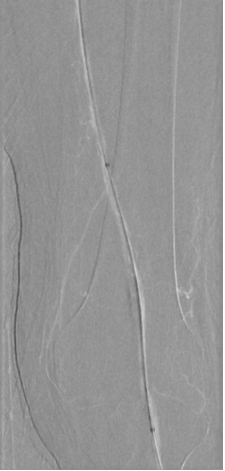

图为:导丝进入ATA,远端无法回真腔

图为:足背动脉穿刺对接

图为:药涂球囊扩张图为:药涂球囊扩张